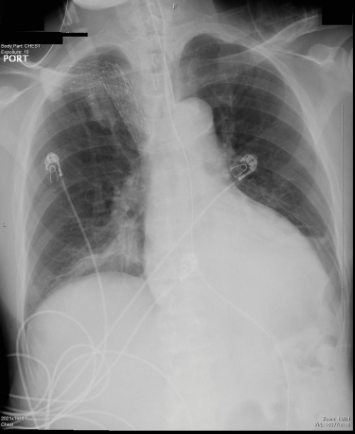

患者59岁,男性,有高血压、房颤和终末期肾病(ESRD)的血液透析病史,因精神状态改变和呼吸急促而被送往急诊科。在被送到急诊室时,患者出现呼吸困难。体格检查发现胸部听诊有双侧啰音,颈静脉扩张并伴有双侧下肢水肿。随后患者被插管并送入重症监护室。他最初的生命体征满足高血压急症的证据,血压为221/117 mmHg,脉搏率(bpm)为99次/分钟,体温(T) 36.7 °C。患者错过了他的上一次血液透析(HD ),实验室检查显示显著的高钾血症,肌钙蛋白血症和高氨血症。初步检查显示胸片(CXR)显示肺水肿,未见白细胞增多初步检查显示胸部x光(CXR)显示肺水肿,但无白细胞增多(图1)。头部CT未见明显异常。

图1、胸部x光(CXR)显示肺水肿